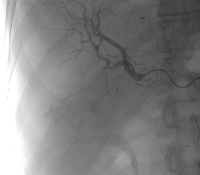

Πρόκειται για άνδρα ασθενή 58 ετών, ο οποίος υποβλήθηκε σε αξονική τομογραφία για επιγαστραλγία. Διαπιστώθηκε μάζα στην ουρά του παγκρέατος μεγέθους 5 εκατοστών, καθώς και πολλαπλές (περίπου 50) ηπατικές μεταστάσεις (εικόνες 1, 2). Βιοψία μίας από τις ηπατικές μάζες ανέδειξε νευροενδοκρινές καρκίνωμα καλής διαφοροποίησης. Ο ασθενής υποβλήθηκε σε ουραία παγκρεατεκτομή με σπληνεκτομή (εικόνα 3), αριστερή ηπατεκτομή μετά του 1ου τμήματος (εικόνα 4), τέσσερεις άτυπες δεξιές ηπατεκτομές και πολλαπλές κατευθυνόμενες (IOUS) εστιακές καταστροφές με μικροκύματα (εικόνα 5). Ογκομετρική αξονική την 7η μετεγχειρητική ημέρα ανέδειξε μείωση του μεταστατικού φορτίου σε ποσοστό > 90%. Κατόπιν, την 6η και 10η μετεγχειρητική εβδομάδα, ο ασθενής υποβλήθηκε σε διαδοχικούς υπερεκλεκτικούς (πρόσθιο και οπίσθιο) εμβολισμούς της δεξιάς ηπατικής αρτηρίας (εικόνα 6, απεικόνιση του πρόσθιου μετά από εμβολισμό του οπίσθιου τομεϊκού δεξιού αρτηριακού κλάδου). Οctreotide-scan τη 12η μετεγχειρητική εβδομάδα ανέδειξε απουσία ενεργών νευροενδοκρινών εστιών. Ο ασθενής λαμβάνει Sandostatin LAR εφ' όρου ζωής.